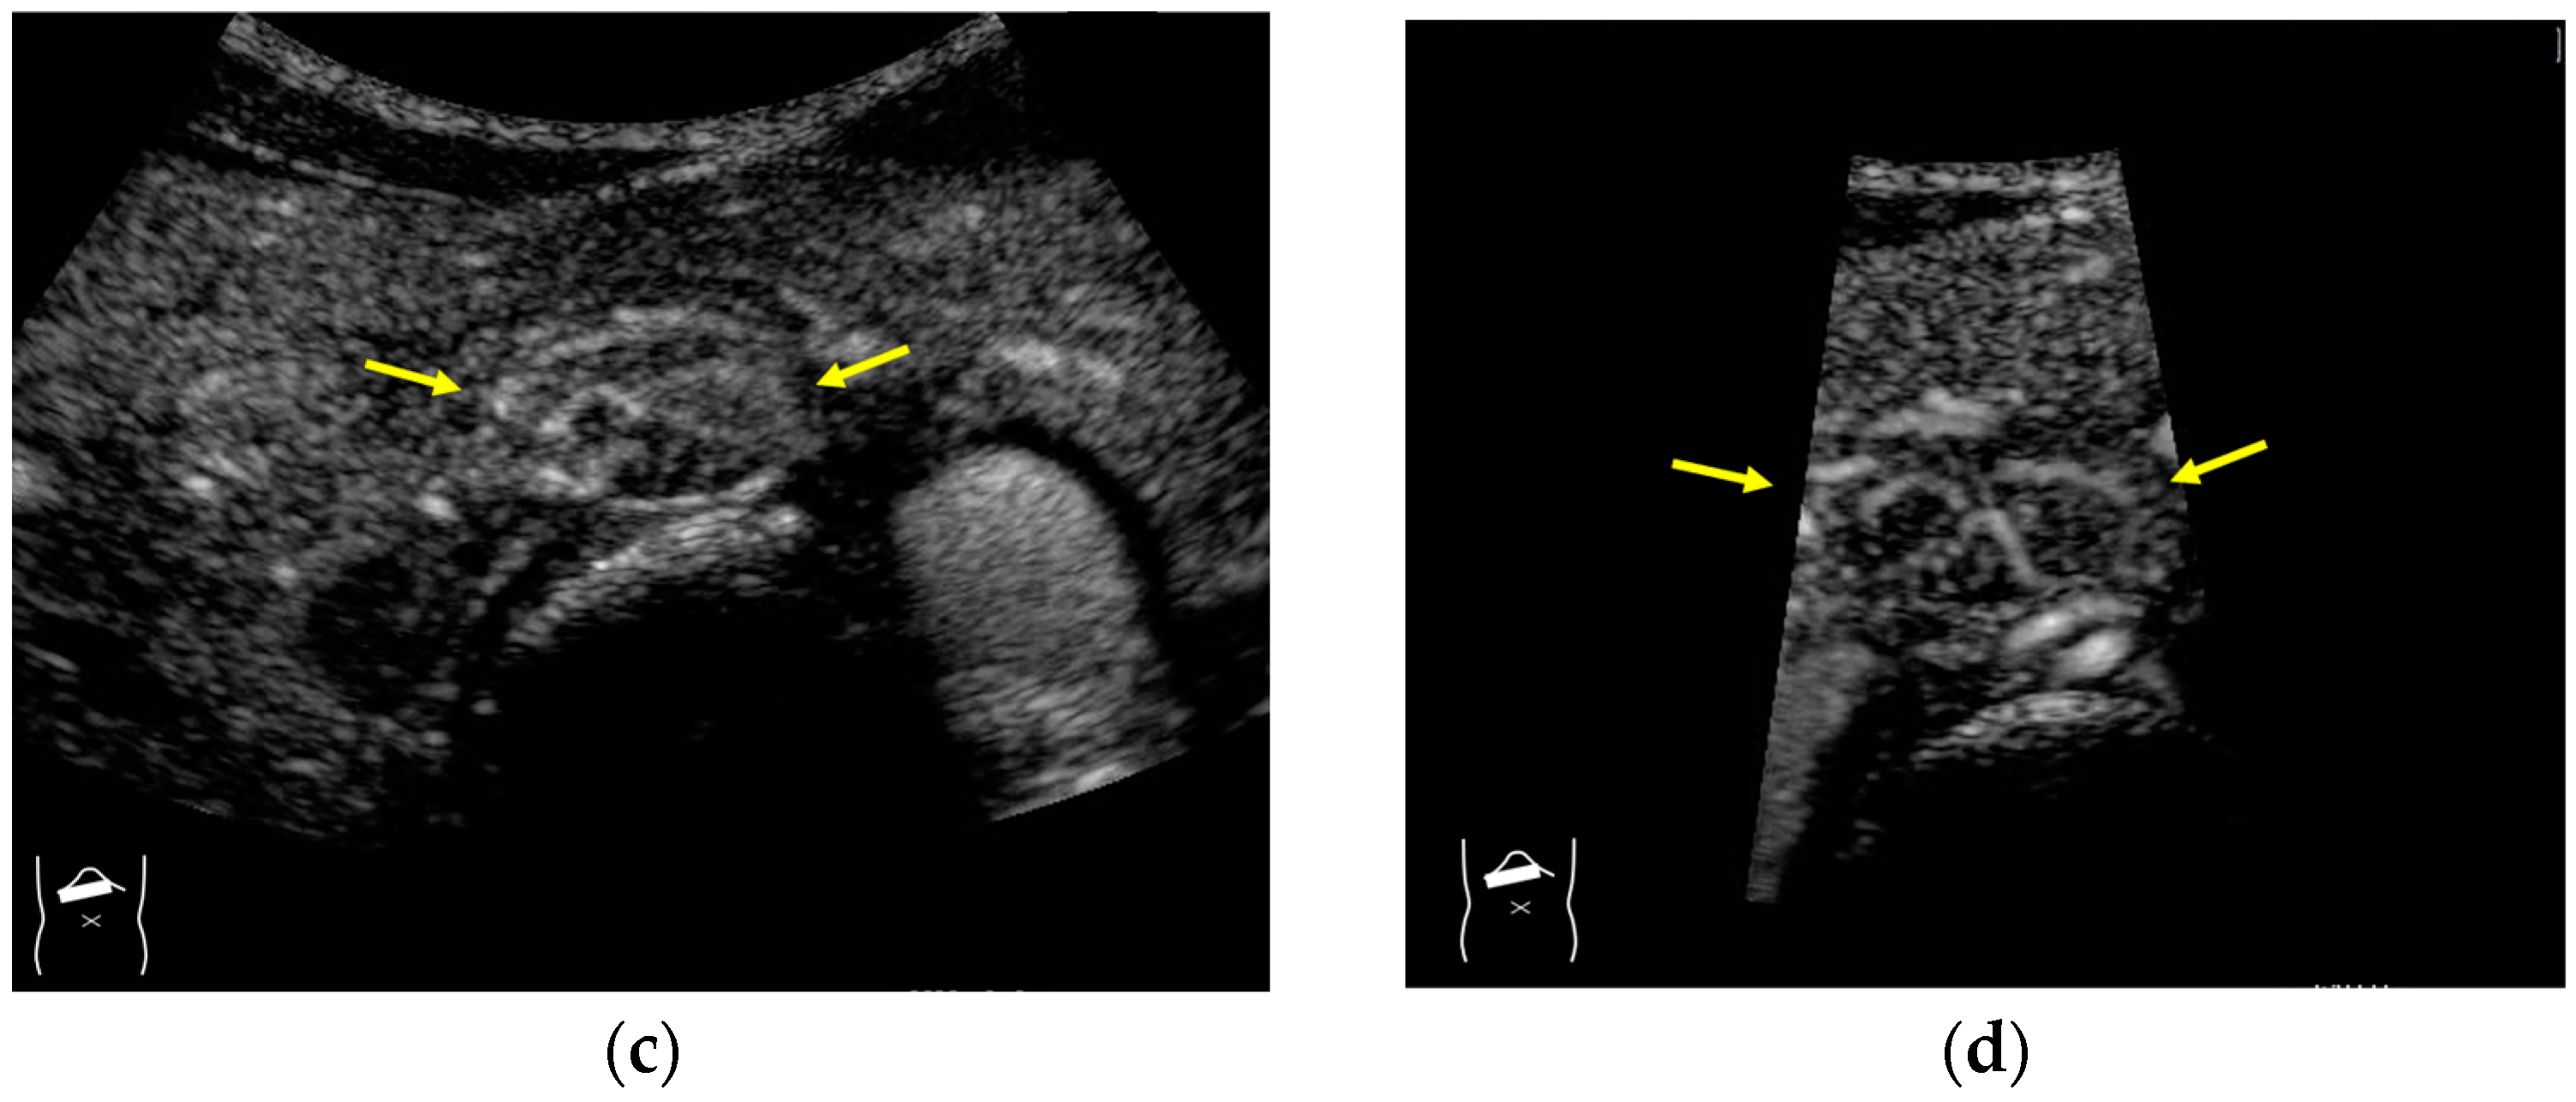

Next, we discuss the pulse inversion (PI) method and the amplitude modulation (AM) method, which are two representative modes that are frequently used in CEUS examinations [33]. Since there are some differences between the CEUS images obtained using these two methods, it is necessary to distinguish between them when performing CEUS examinations. As shown in Figure 2, the PI method is based on the sum of the first pulse and its inverted second pulse. If the tissue does not move between these two pulses and only the signal from a bubble remains unstable, then only the signal from the bubble is displayed with no background information (Figure 2a,b). In practice, however, the background signal is often not fully eliminated because of slight tissue movement. The AM method attempts to alleviate this problem of a “sooty” background. In the AM method, instead of two inverted pulses of the same magnitude (1-1), three pulses of the form 1/2-1+1/2 are emitted and summed to ensure the elimination of the signal from the background (Figure 2). Actual clinical images are presented. As shown in Figure 2, the AM method improves diagnostic accuracy by eliminating high-echo areas in the background. However, it also has the disadvantage that the image’s real-time nature is reduced as the number of US pulses increases. These two modes are available in most of the current high-end machines, but the current guidelines do not illustrate their proper use [34,35]. This increases flexibility for diagnosticians but also causes difficulties in choosing the right CEUS mode, resulting in randomness in mode selection. The basic strategy is to use one mode after another for comparison. However, the most simple and reliable method is to use the AM mode when the target lesion is highly echogenic (Figure 2c) and to otherwise use the PI mode. Nevertheless, individual adaptation should be determined each time to balance the optimal CEUS image quality, namely the maximal signal separation between the tissue and contrast medium and the optimal frame rate. However, the frame rate is crucial for accurately recording the beginning of the wash-in and wash-out. A frame rate of 10 frames/s or more is usually considered for liver tumor characterization [33].

Figure 2.

Amplitude modulation vs. the pulse inversion method: (a) Schematic drawing of pulse inversion (PI) mode. Substraction a − b = residual echo. (b) Schematic drawing of amplitude modulation (AM) mode. Substraction (a + c) − b = residual echo. (c) Gray-scale US shows a 4 × 4 cm heterogeneous mass (metastasis from colon cancer) (arrows) in the segment 6 (c). CEUS in amplitude modulation mode clearly demonstrates a punched out defect, leading to the diagnosis of liver metastasis (arrows) (d). CEUS in pulse inversion mode shows a heterogeneous detection (arrows) in a later phase (e).